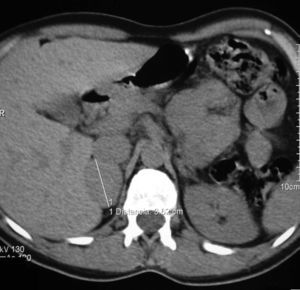

Caso 2: paciente diagnosticada de NF-1 a los 9 años tras el diagnóstico materno (caso 1). A los 15 años consultó por episodios de cefaleas y palpitaciones. En la exploración física destacaban más de 6 manchas café con leche y una TA de 154/83mmHg. Analítica general con glucemia basal de 128mg/dl sin otras alteraciones y TC craneal y evaluación cardiológica normales. Se solicitaron catecolaminas y metanefrinas urinarias con los siguientes resultados: adrenalina: 150mcg/24h (VN: 0,5-20mcg/24h), noradrenalina: 713mcg/24h (VN: 14-80mcg/24h), metanefrina: 1.757mcg/24h (VN: 86-320mcg/24h), normetanefrina: 3.967mcg/24h (VN: 129-400mcg/24h). La RMN describió un nódulo adrenal izquierdo de 4×4×3,8cm hiperintenso en T2, heterogéneo y con zonas necróticas (fig. 2). La MIBG mostró una hiperfijación suprarrenal izquierda. La paciente fue intervenida por vía laparoscópica tras un tratamiento con fenoxibenzamida a dosis de 20mg/12h, confirmándose en la anatomía patológica el diagnóstico de feocromocitoma.